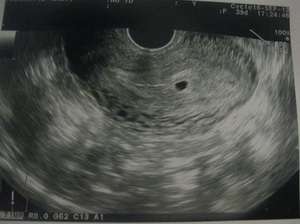

Ультразвуковая диагностика

Третья акушерская неделя не является обязательным сроком для проведения ультразвукового исследования, однако это время предоставляет возможность для тщательной оценки состояния плода и уточнения срока беременности. На первом триместре врач, проведя необходимые измерения и сопоставив их с соответствующими таблицами, сможет довольно точно определить срок беременности, основываясь на размерах эмбриона. В последующие месяцы внутриутробного развития плоды могут значительно различаться:

Поэтому в первые недели беременности ультразвуковое исследование позволяет с высокой точностью установить срок беременности.

Кроме того, ультразвуковая диагностика помогает выявить внематочную беременность и такие состояния, как замершая (неразвивающаяся) беременность. В современной медицине существуют бережные методы, которые, при своевременном обращении к специалисту, могут помочь сохранить репродуктивные функции женщины, что в будущем даст ей возможность стать матерью.